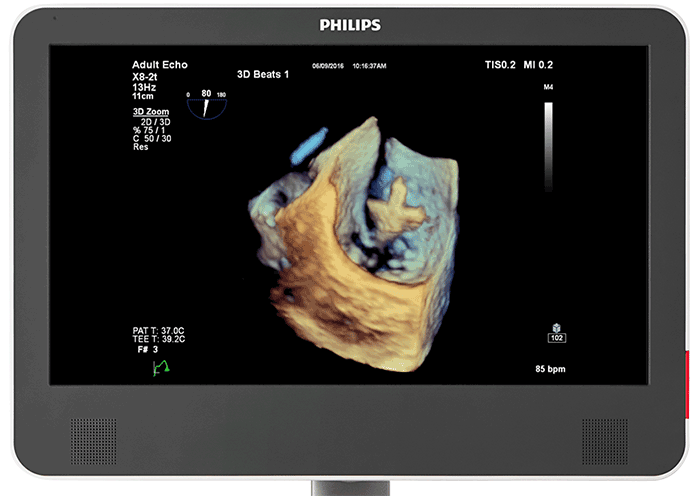

仮想光源によるフォトリアリスティックな3D画像 心臓組織用 TrueVue と仮想光源により、欠損部位や構造の奥行きの把握が容易になり、経胸腔の心臓組織および経食道エコーの視覚化も向上します。新型 EPIQ CVx Transcend を見た臨床医の 90%⁵が、新しい TrueVue 3D フォトリアリスティックレンダリングにより組織構造がより理解しやすく表示されるため、臨床的確信を強く持つことができると回答しました。

次世代 Live 3D TEE 用の設計 X8-2t Live 3D 経食道トランスジューサの音響設計では、より高い周波数と広い帯域幅により、2D および Live 3D での分解能が上がり、心筋組織の詳細が表現されるようになりました。その結果、Live 3D および Live 3D カラーにおいて、画質を犠牲にすることなく、真の意味でのワンビート画像取得とフィリップス史上最高のボリュームレートが実現しました。ハンドルには、リアルタイムで設定可能なファンクションボタンが搭載され、検査中でも追加機能を使用できます。